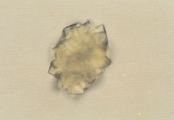

Биллирубин может кристаллизоваться в моче, формируя желто-красные или красно-коричневые узелки или гранулы (рис. 1). Кристаллы биллирубина могут быть обнаружены в высококонцентрированной моче здоровых собак. Если они обнаруживаются в большом количестве, в нескольких образцах мочи подряд, то это говорит о нарушении метаболизма биллирубина.

Рис. 1. Микрофотография кристаллов биллирубина в мочевом осадке годовалого кобеля